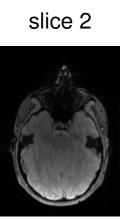

To verify the in-vivo applicability, human brain images of a healthy volunteer were acquired using the above described GRE sequence modified to include the optimized CAIPIRINHA-based pulses. The sequence parameters were set to , , bandwidth , matrix size and FOV . After acquisition, the k-space data of the individual slices were separated using an offline slice-GRAPPA ( coils, kernel size of ) reconstruction [42, 9]. The reference scans used in the slice-GRAPPA reconstruction were performed with the same sequence using an optimized single-slice pulse (not shown here). To decrease the scanning time, we acquired k-space lines ( of the full dataset) around the k-space center for each reference scan. After this separation, a conventional Cartesian reconstruction was performed individually for each slice.

Figure 6 shows the image reconstruction using optimized RF pulses for simultaneous excitation of two, four and six slices with the same slice separation and thickness as above. As can be seen clearly in the first column, all three pulses lead to the desired excitation pattern in-vivo as well. The remaining columns show the slice-GRAPPA reconstructions, which illustrate that the excitation is uniform across the field of view.